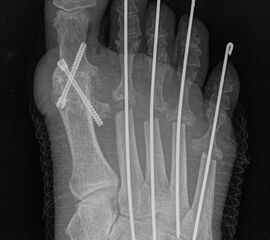

Abschließend erfolgt die temporäre K-Daht Fixation sämtlicher Kleinzehen in achsgerechter Stellung. Die Strecksehnen werden in Verlängerung vernäht.

Die Operation nach Hoffmann-Tillmann (Abb. 4) ermöglicht durch die Resektion der Metatarsaleköpfe die Reposition der Zehen, da hierdurch der notwendige Platz geschaffen wird (Tillmann 1990). Meist sind nicht nur die knöchernen Strukturen der Metatarsaleköpfe destruiert, auch das plantare Polster ist disloziert, regelmäßig kommt es zur Ruptur der plantaren Platten mit Destruktion der Kapsel-, Band- und Sehnenstrukturen (Tillmann 2009) 6. Häufig findet man ausgeprägte Rheumaknoten oder Bursitiden plantar. Durch die breite, querovaläre Hautexzisionaus dem Vorfußballen werden plantare Schwielen entfernt, später beim Hautverschluß werden die plantaren Strukturen durch die plastische Dermatodese wieder in die Belastungszone reponiert.

Es sollten immer alle MT Köpfe II-V reseziert werden, um einen harmonischen Metatarsale Index mit genauer Längenabstimmung herzustellen und keine Druckspitzen durch überlange Metatarsalia zu provozieren. Die kann in Einzelfällen bedeuten, dass ein weniger destruiertes Gelenk zwischen oder am Rand der metatarsalen Reihe geopfert werden muss. Die Operation nach Hoffmann-Tillmann wird meist ab LDE Stadium IV und V indiziert (Tabelle 1).